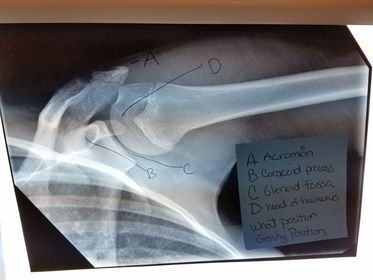

Glenoid Cavity Posterior Oblique Shoulder *nontrauma "Grashey Method" *SPECIAL 40 SID 70-85 kVp 10x12 IR grid CR perpendicular to IR, centered to scaphohumeral joint - 2 in inferior and medial from the superolateral border of shoulder *expose on suspended breath *pt obliqued 35-45 degrees toward the affected side - opens up glenoid cavity

A. coracoid process B. glenoid cavity OR scapulohumeral joint C. spine of the scapula D. acromion